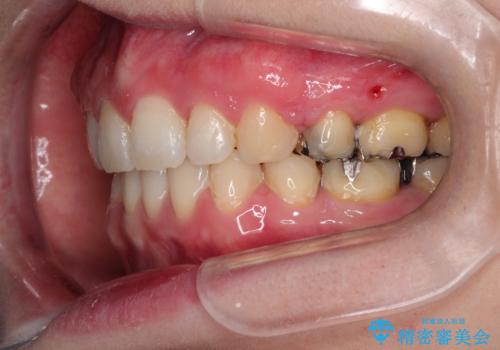

- 口が閉じずらく、口元が突出している状態でした。

上下左右の歯を1本ずつ、合計4本抜歯して、ワイヤーにて矯正することとなりました。

もともと下の前歯の永久歯が1本欠損しており、抜歯部位の選択を考慮しなければならない症例でした。シミュレーションを事前に行い、下顎の抜歯部位を決定しました。